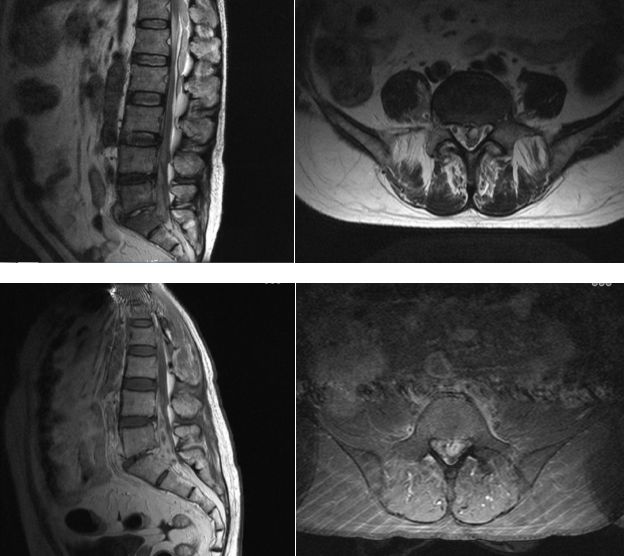

入院第3天,患者在全麻下行经皮内镜经椎板间入路脓肿清除引流术,分别经L4/5及L5/S1椎板间入路,清除相应节段硬脊膜腹侧及神经根周围感染灶(图2A),留取部分炎症组织送病理及培养涂片,于L5/S1间隙留置引流管1根,术后持续负压吸引,并予万古霉素 1g q12h+美罗培南1g q8h抗感染治疗。

术后病理证实为感染化脓性炎症(图2B)。患者疼痛症状明显缓解,左下肢肌力较术前改善,经继续予抗感染治疗,术后2周复查白细胞计数4.9×10^9/L,超敏C-反应蛋白5.6mg/L,炎症控制满意,切口愈合良好(图2C)。MRI复查显示局部减压效果良好,硬膜外脓肿占位消失(图3)。

图2. A.内镜下见神经根充分减压;B.术后病理 (椎管内脓肿)纤维脂肪组织,伴急慢性炎症细胞浸润;C.手术伤口。D.术后CT骨窗重建。